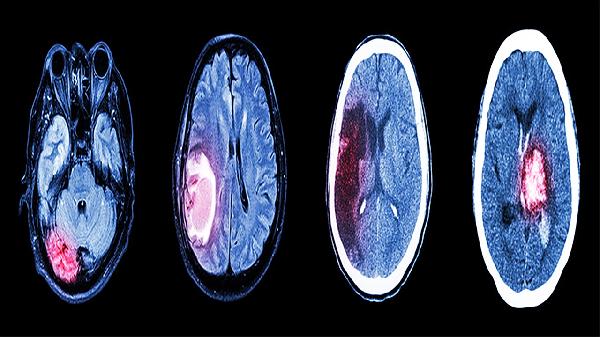

颅脑损伤是指由于外伤或疾病导致的脑组织损害,包括轻微脑震荡、脑挫裂伤、颅内血肿等。轻度损伤多表现为短暂头晕、记忆缺失,而严重者可能出现意识丧失、语言障碍甚至瘫痪。大脑是人体功能的“中枢指挥室”,其损伤会波及多方面的生理和认知功能,因此康复情况差异较大。

轻中度颅脑损伤在合适的医疗干预下,通常恢复较好,神经系统具有一定的自我修复能力。然而,严重颅脑损伤可能导致神经细胞永久性损害,恢复则需要长期的康复训练,例如物理治疗、语言训练、以及认知能力的再教育等。同时,恢复过程中可能会出现记忆力下降、情绪波动等后遗症,这些需要逐渐适应并寻找专业心理辅导。